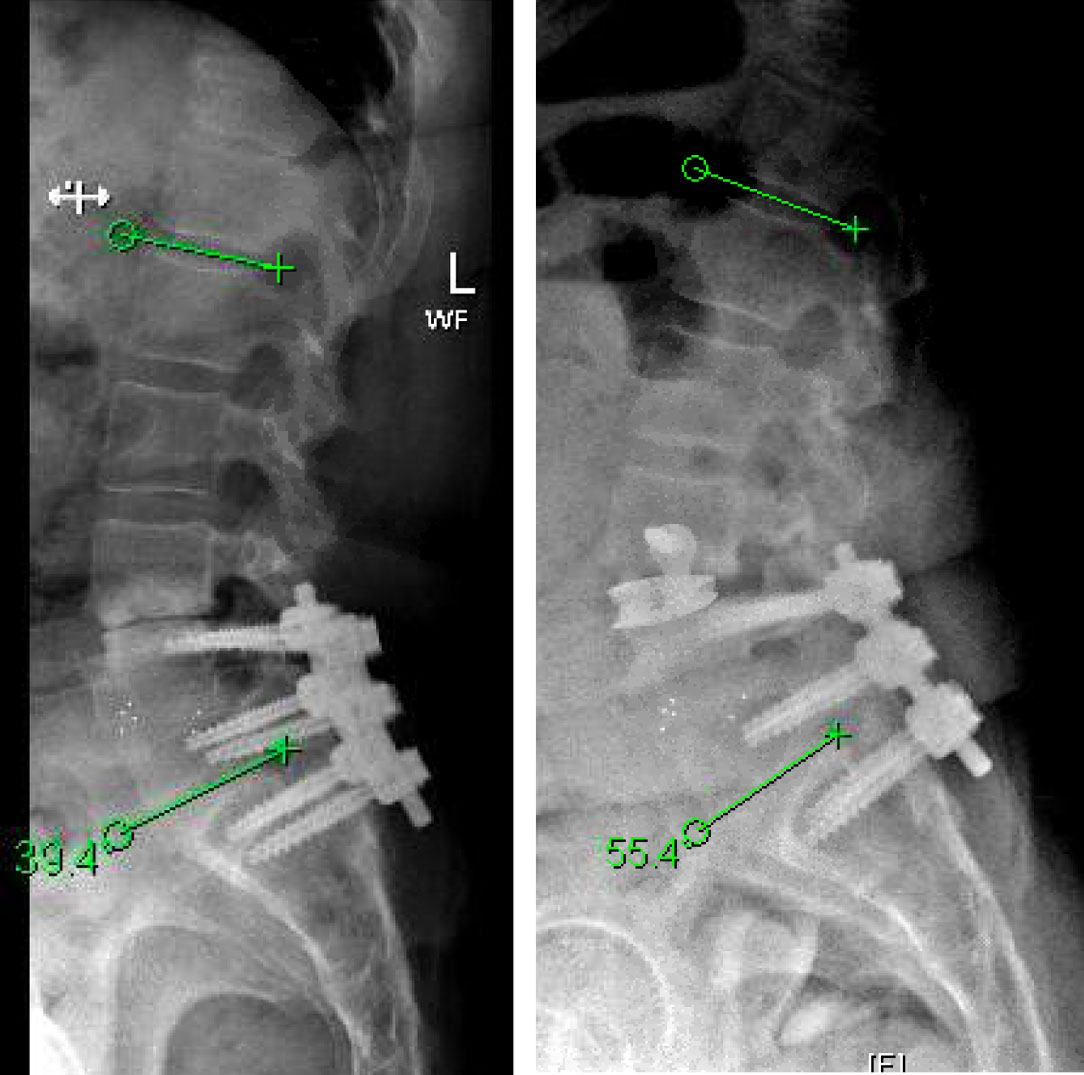

The goals of surgery were to achieve spinal stability, neural decompression, and re-establish a physiologic sagittal alignment. She had co-morbidities that precluded a more conventional open posterior approach with hardware revision. We therefore elected to perform an L3-4 Minimally Invasive Direct Lateral Interbody Fusion with Plate. This allowed for stability through the interbody device and lateral plate, indirect neural decompression by distracting the spinal canal and neuroforamina, and increase lordosis by lengthening the anterior aspect of the spine with placement of a hyperlordotic cage.

Patient tolerated the surgery well and attained near complete relief of her preoperative leg pain and chronic back pain. Incision was a little over one inch on her lateral side. Her postoperative pain was less significant given the indirect access to the spine which allowed for preservation of her paraspinal musculatures, and minimally invasive approach which maintained the integrity of the lateral muscle. She was discharged home on the day after surgery and was able to fully wean off her chronic narcotics.